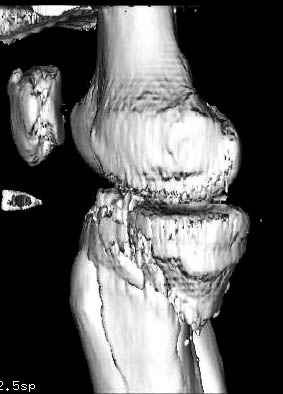

Такая ситуация характерна для многих, когда принимается ошибочное решение, т.е пытаются фиксировать одним имплантом переломы двух мыщелков. Латеральная пластина приемлема только для тех случаев, когда сохраняется интактным медиальный диафизарный кортекс и отсутствует фрагментация на верхушке медиального перелома.

Здесь как раз тот случай, когда результат зависит не только от мастерства хирурга, но и от наличия современных методов исследования. Например, КТ которая поможет рассчитать направления шурупов и установку импланта. Кроме этого, поможет определиться с доступом.

На представленных предоперационных срезах КТ огромный задне-медиальный фрагмент расположен больше кзади, чем медиально. Для планирования, кроме поперечных срезов, надо ориентироваться на корональные срезы, которые укажут топографию верхушки медиального фрагмента.

Надеюсь, представленные снимки разных случаев помогут разобраться в тактике, и критика примется без личной обиды.